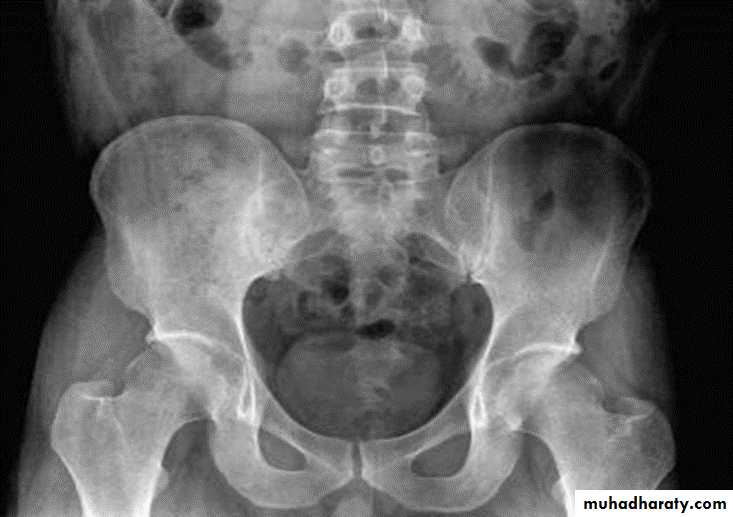

ANKYLOSING SPONDYLITIS (AS)

Seronegative spondyloarthropathy of the axial skeleton and proximal large joints.

Clinical: males >> females. HLA-B27 in 95%. Insiduous onset of back pain and stiffness. Onset: 20 years.Radiographic features:

* SI joint is the initial site of involvement:

bilateral, symmetrical

Erosions: early ,Sclerosis: intermediate , ankylosis: late

* Arthritis of proximal joints (hip > shoulder) in 50% ,erosions and osteophytes